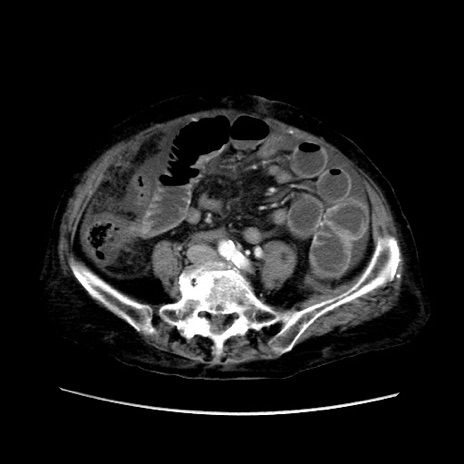

症例31(横断像)

【症例】80歳代 女性

【主訴】腹部膨満感

【現病歴】他院にて肝硬変にてフォロー中。1週間前から便秘、腹部膨満感、臍部腫瘤あり受診となる。

【既往歴】肝硬変

【身体所見】腹部膨隆あり、皮膚変化なし、疼痛なし。

【データ】WBC 4600、CRP 0.25